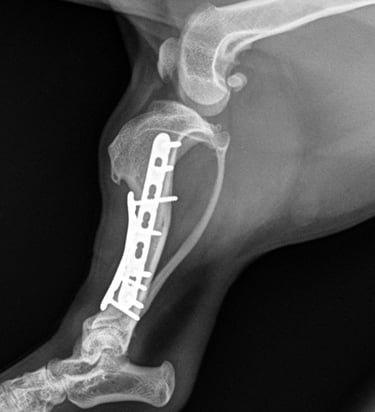

Case 5 - Bonnie

Tibia fracture - Mini Dachshund, 2y, female